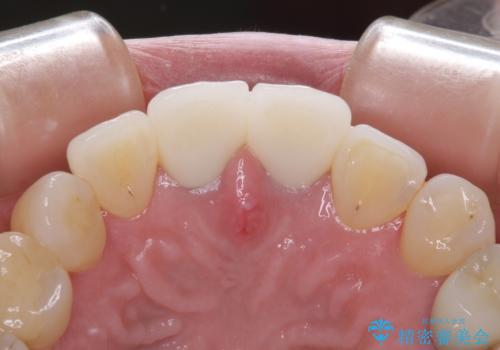

- 治療中の前歯の仮歯がひどい状態であるとのことで来院された患者様です。

治療中の前歯は根管治療の途中であり、根尖部に痛みを感じる状態でした。

まずは審美的な仮歯を装着し、根管治療を行った後にオールセラミッククラウンにて補綴治療を行うこととしました。

根管治療後に痛みは軽減しましたが、僅かな痛みが続くとのことで、レントゲン写真では病変は認められなかったものの、歯根端切除を行うこととしました。処置後は痛みは全くなくなり、安心して補綴治療を行うことができました。